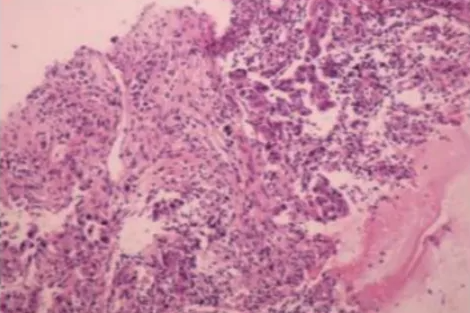

于是,该案例经多学科会诊后,专家们考虑不排除“假性进展”,故行肺部病灶穿刺活检,看到肺腺癌伴大量坏死及淋巴细胞浸润(图2),证实为假性进展,遂继续当前治疗方案,免疫治疗2周期后病灶缩小,达到部分缓解(PR)。患者于2020 年 2 月 18 日复查维持 PR 状态,并继续使用免疫治疗药物维持。在后续治疗过程中,患者未再出现关节肿痛,也无其他不良反应发生。随访至2020 年 5 月 18 日,未见肿瘤复发转移。

图2 假性进展后病理检查